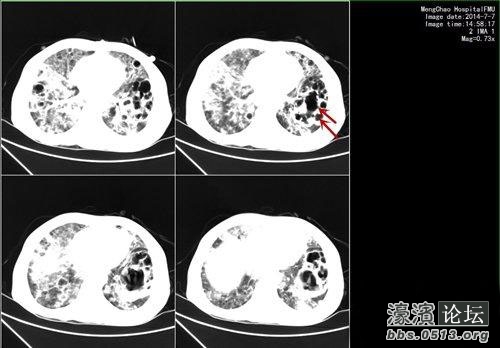

1 L3 D* k4 Q! a" U& y6 r% ]! u% k! | 2个月前,黄萍突然发烧,还咳嗽,咳出黄色的浓痰并伴有气促。她在莆田当地医院挂了三天的抗生素,还是高烧40℃,后被转诊到福建医科大学附一医院,她的肺部CT片子显示出一个又一个空洞,大的有橘子(6厘米×7厘米)大小,小的也有圣女果(3厘米×2厘米)大小。! v8 @) M+ }7 B/ e; V) q3 g6 [2 l

0 E- R$ {: @' ~( b* X) S, z' H8 w8 i1 M “当时她咳出不少黄脓痰,高热,气促,神志淡漠。”丁海波说,黄萍肺部多发空洞,这些黄脓痰很可能含有坏死的肺部组织。最可怕的是,细菌很可能已经进入血液,又通过血液传播至五脏六腑,造成多脏器的脓肿。她的生命危在旦夕。